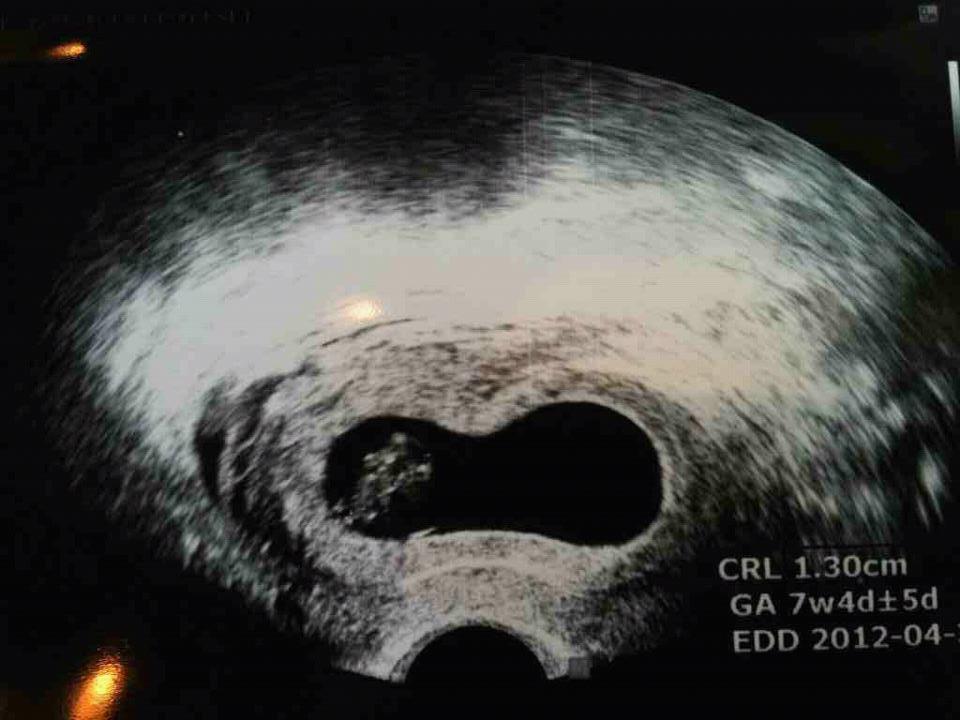

1.3cm

½ÉÀåµµ Àß ¶Ù°í °Ç°ÇÏ°Ô Àß Å©°í ÀÖ´ä´Ï´Ù.

³»³â 4¿ù30ÀÏÀÌ ¿¹Á¤ÀÏ À̶ø´Ï´Ù.